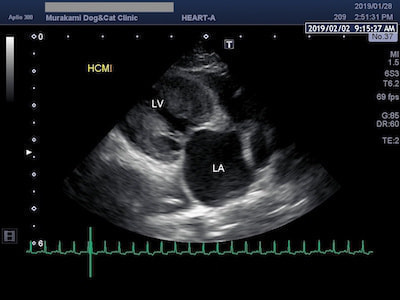

肥大型心筋症(HCM)

心臓の筋肉が肥大してしまう肥大型心筋症(HCM)は、猫の心筋症の中で最も多く認められますが、目立った症状がないまま進行することも多く、肺水腫や動脈血栓塞栓症などの重篤な状態になって初めて発見されることが多い疾患です。聴診で心臓の雑音が認められないことも多く、診断には心臓エコー検査を中心とした詳しい検査が必要となります。